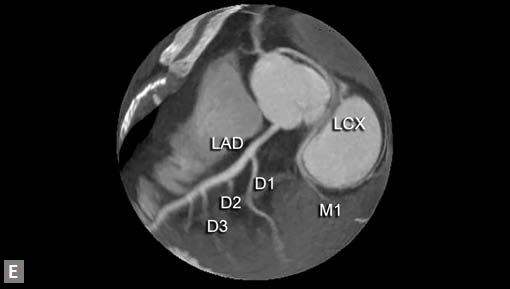

Only few coronary artery anomalies are hemodynamically significant. Some are called “malignant” as they carry potential risk of sudden cardiac death, particularly in children and young adults. These are ectopic origin of coronary artery from pulmonary artery, single coronary artery, interarterial RCA (Figs 21A to E). Interarterial RCA is the most common malignant form. Retroaortic left circumflex artery (LCX) is the most common coronary anomaly and is not of much clinical relevance. The possible explanations for malignant nature of RCA are compression between aorta and RVOT, particularly during exercise, acute curve, aberrant shape and stenosis of ostium of RCA on left sinus of Valsalva. Retrospectively gated CT is the ideal modality to confirm the diagnosis of malignant RCA.

Very rarely compression of RCA between aorta and RVOT/ MPA can be demonstrated by evaluating the images in various phases of cardiac cycle. More malignant variety is LM arising from right sinus of Valsalva and having interarterial course. More than 30% of these individuals have sudden death. Anomalous Origin of Left Coronary Artery from